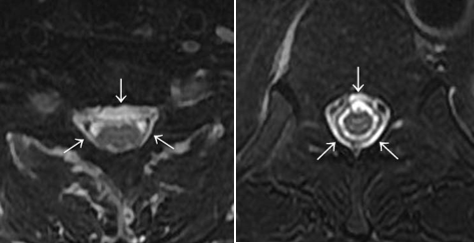

iFDSS・DTSについて

(1)iFDSS(incomplete FDSS):局所の微細(不完全)硬膜外水信号

また、令和2年2月第19回日本脳脊髄液減少症研究会(神戸)の特別講演にて、研究班画像診断担当の鹿戸先生(山形大学放射線診断科教授)に当院症例よりiFDSSの見本例を選定していただい画像の一部を載せる(図C)。このような所見を硬膜外腔の微細水信号(iFDSS)=脳脊髄液漏出所見と考えている。

図C